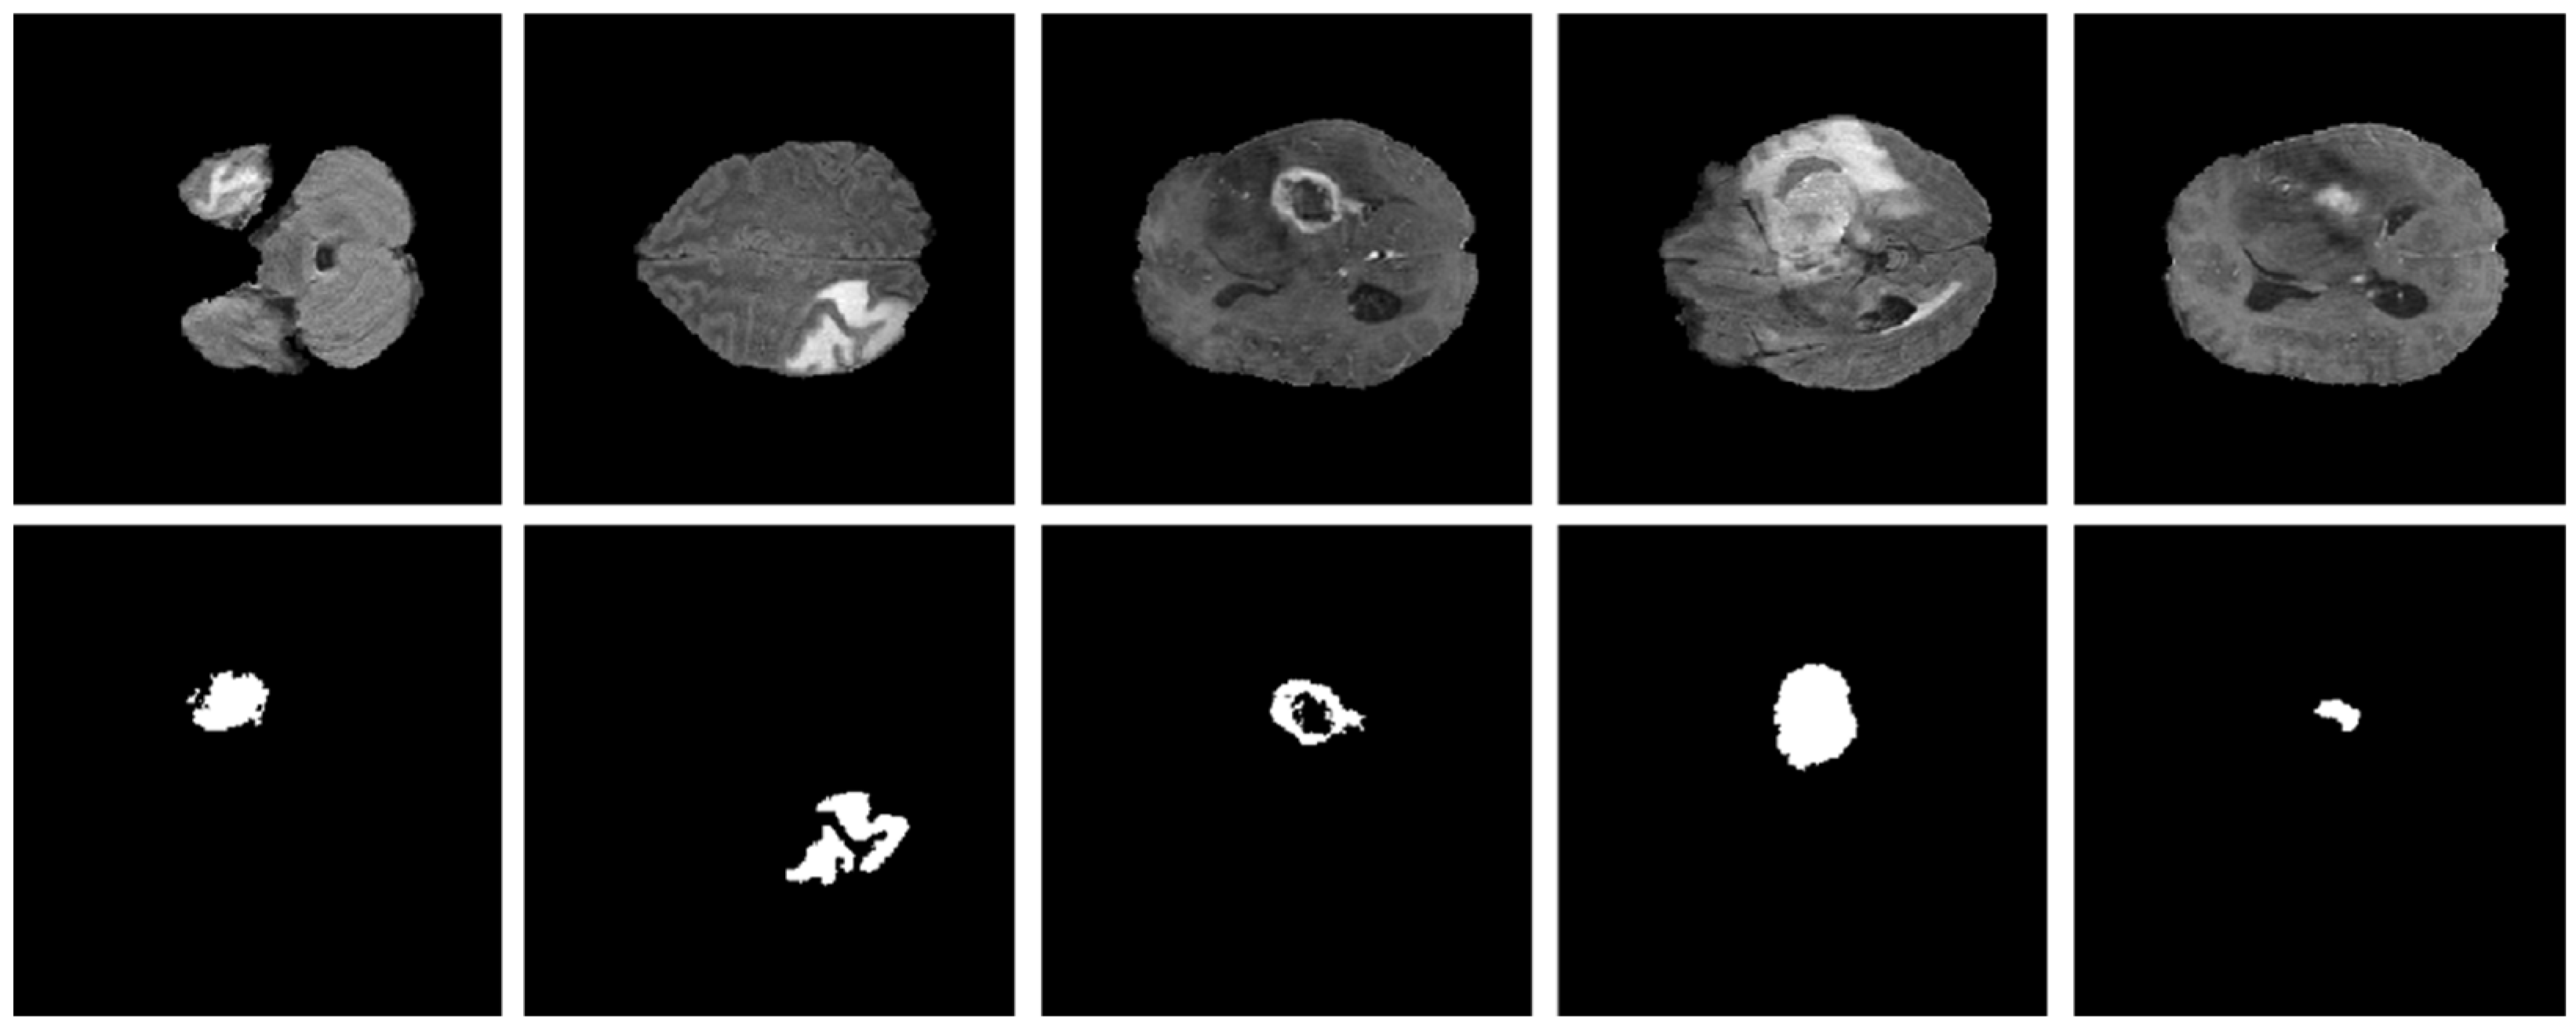

As explained in Section 3.1, the proposed model was evaluated using two BT datasets from BraTS-2020 [9,22,23] as Dataset-1, and the brain tumor progression dataset [64,65] as Dataset-2. For the homogeneous dataset analysis, a five-fold cross-validation was performed using Dataset-1. Dataset-1 consisted of 369 patients, including 293 diagnosed with HGG and 76 with LGG, with four modalities including post-contrast T1-weighted (T1ce), T1, T2, and Flair. We used the T1ce and Flair modalities for their rich visual representations of tumor regions compared to other modalities. This rich dataset has been instrumental in advancing the research and development of CAD (computer-aided diagnostic) frameworks for BT segmentation. Dataset-1 is a combination of different structures of MRI BT, including gadolinium-enhancing (ET), peritumoral edema (ED), necrotic core (NCR), and non-enhancing core (NET). The diffused, irregular, and nonspecific enhancement of ET, the varying distribution and heterogeneity of ED and NCR, and coexistence of NET with ET make segmentation more challenging. The annotations of this dataset for training data are publicly accessible, whereas the annotations for test trials are not disclosed. Examples from Dataset-1 are shown in Figure 4.

Figure 4.

Examples of brain tumor scans in the first row, with corresponding segmentation masks in the second row from Dataset-1.